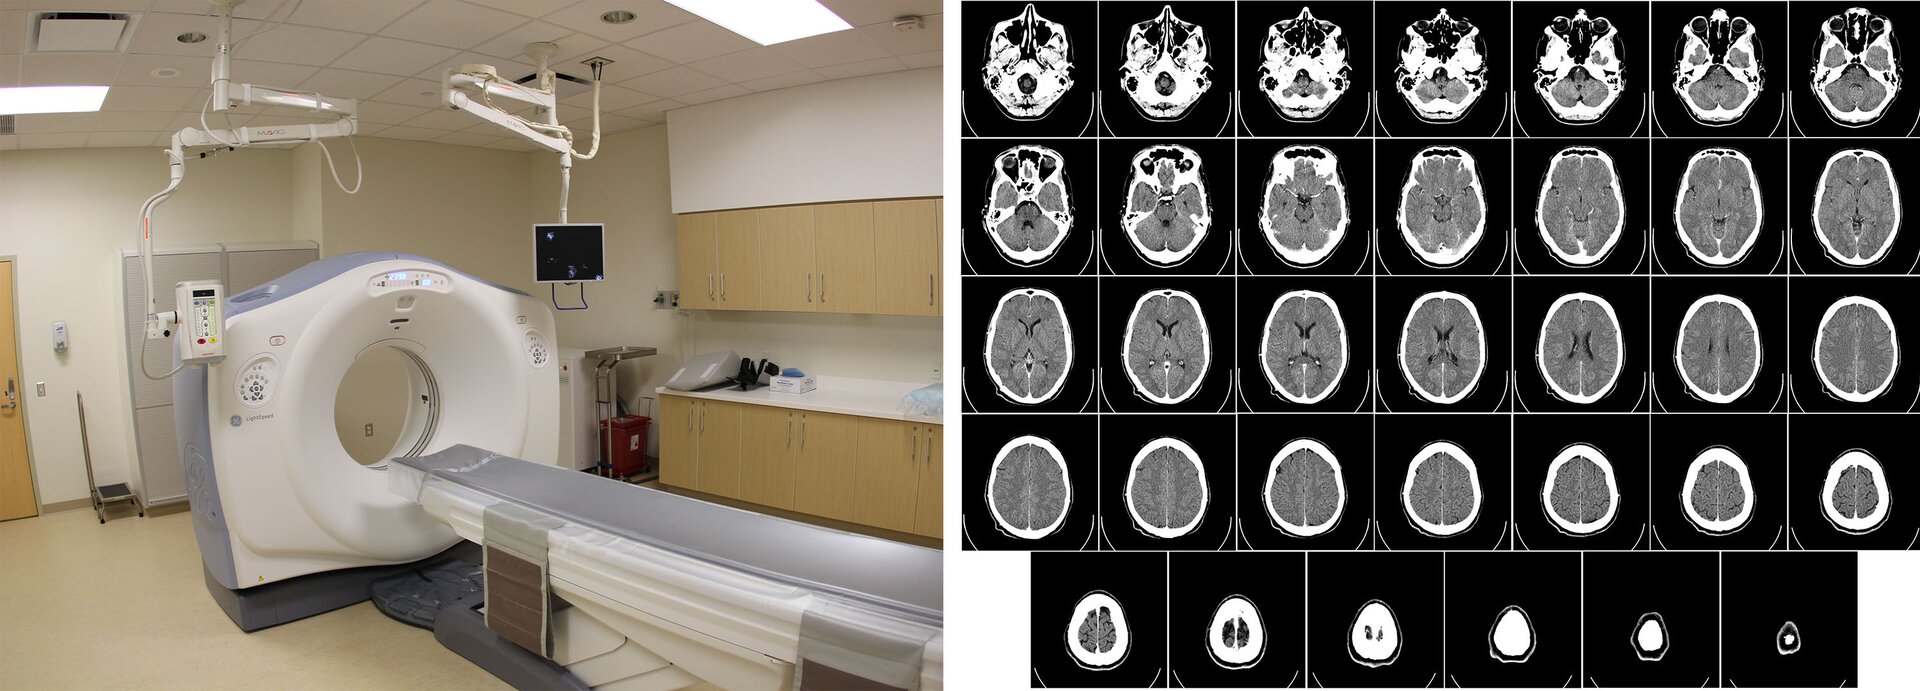

W ostatnich czasach rozwinęła się dokładniejsza metoda badań diagnostycznych przy pomocy promieni rentgenowskich – tomografia komputerowa. Pozwala ona zobaczyć w przekrojach wnętrze badanego ciała człowieka.

Uproszczony schemat tomografu pokazano na Rys. 1. Wokół pacjenta znajduje się układ wielu detektorów promieniowania rentgenowskiego, ułożonych w kształcie pierścienia. Liczba detektorów może sięgać kilku tysięcy.

Wewnątrz nieruchomego układu detektorów porusza się po okręgu lampa emitująca promieniowanie rentgenowskie, które rejestrowane jest przez detektory umieszczone po przeciwnej stronie. Promieniowanie, pochłaniane przez narządy wewnętrzne pacjenta, tworzy wiele obrazów widocznych pod kolejnymi kątami. Zarejestrowana seria obrazów rentgenowskich opracowywana jest z pomocą programu komputerowego, który wykonuje rekonstrukcję przestrzenną elementów pochłaniających promieniowanie, czyli narządów wewnętrznych pacjenta. Na Rys. 2. pokazano wygląd tomografu oraz przykładowy obraz zrekonstruowany tomografem komputerowym.

W medycynie promieniowanie rentgenowskie wykorzystuje się także w terapii antynowotworowej. Promieniowanie jonizujące skuteczniej niszczy komórki nowotworowe, aniżeli komórki prawidłowe. Po serii naświetleń, guz nowotworowy zmniejsza się i zanika. Oczywiście terapia promieniowaniem rentgenowskim wymaga dokładnego zlokalizowania guza i zaplanowania dawek naświetleń. W tym celu pomocna jest tomografia komputerowa (Rys. 2 b).